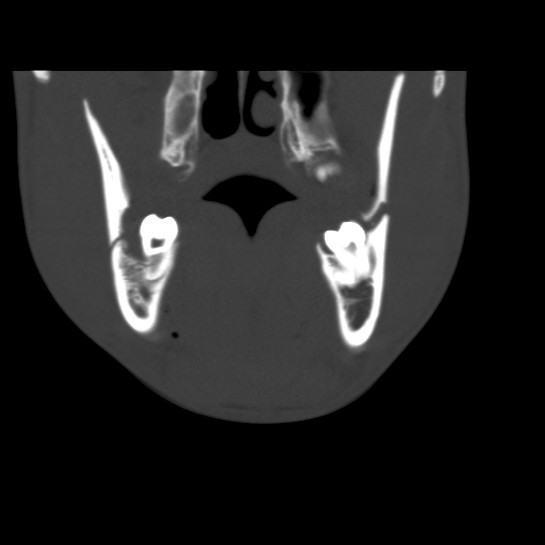

Facial Fracture X-Rays